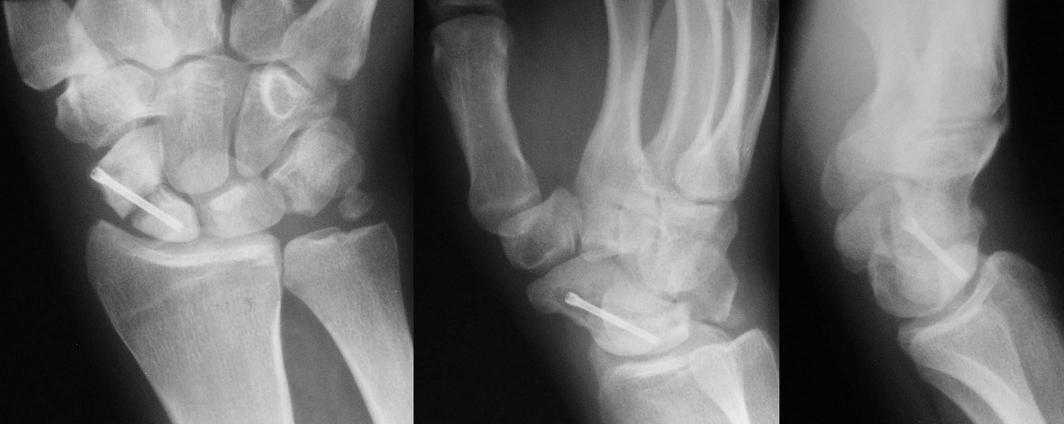

I am not sure if the differential of a nonunion vs. pseudoarthrosis means much in this context. The distal pole of the screw has a lucency, so the

nonunion is most likely unstable and moving. It needs revision. The radial styloid does not have evidence of DJD, so I do not think it needs to be resected. The surgery will probably require an open revision, removal of necrotic bone and soft tissue interposition, and would benefit from some

distal radial autograft. The patient needs to refrain from smoking and I would use a case to be sure they do not move for a while. A stiff wrist is not a bad outcome; a bad outcome is a painful wrist.

1. Подвывих полулунной кости до конца не устранен-боль.

2. Сделайте КТ кистевого сустава и вы объективно оцените степнь консолидации ладьевидной кости.

>>Подвывих полулунной кости до конца не устранен-боль.

О каком подвывихе полулунной кости идёт речь, если эта кость единственная на протяжении всего времени после травмы оставалась там, где ей и положено? Или же все остальные запястные кости продолжают оставаться в подвывихе? По моему скромному мнению в межзапястных суставах всё конгруэнтно.

>>Сделайте КТ кистевого сустава и вы объективно оцените степнь консолидации ладьевидной кости

А разве рентгенограмм не достаточно для констатации несращения?

>>Здаётся мне Вы имеете удовольствие видеть ложный сустав ладьевидной кости.

Такое ощущение, что имеющееся состояние ещё не является необратимым (отсутствие склероза отломков на уровне перелома) и обусловлено исключительно нестабильностью (сам винт оказался слабоват или чрезмерные нагрузки привели к срыву фиксации - пациент, заметьте, мотоциклист!)

Почему-то хочется верить, что можно добиться сращения, если вернуть кости стабильность путём компрессионного остеосинтеза более мощным винтом без открытого вмешательства на компрометированной зоне и защитить фиксацию строгим соблюдением режима. Я сильно ошибаюсь?